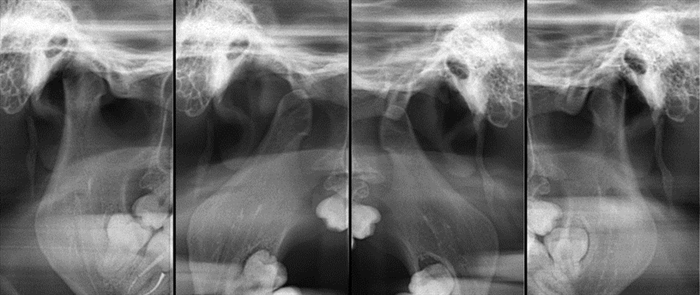

КТ играет существенно меньшую роль в выявлении патологии ВНЧС, чем МРТ, т. к. при этом исследовании можно получить отображение в разных ракурсах только костных отделов суставов с анализом их положения по отношению друг к другу. Мягкотканные компоненты ВНЧС на КТ не определяются. Для их визуализации необходимо производить КТ с контрастированием полости ВНЧС. Исследование проводится во фронтальной и аксиальной проекциях, в положении привычной окклюзии и при максимальном опускании нижней челюсти. По завершении исследования выполняются мультипланарные реконструкции. По реконструкциям, выполненным в сагиттальной плоскости до и после опускания нижней челюсти, определяют степень смещения головки нижней челюсти по отношению к суставному бугорку (рис. 20.30).